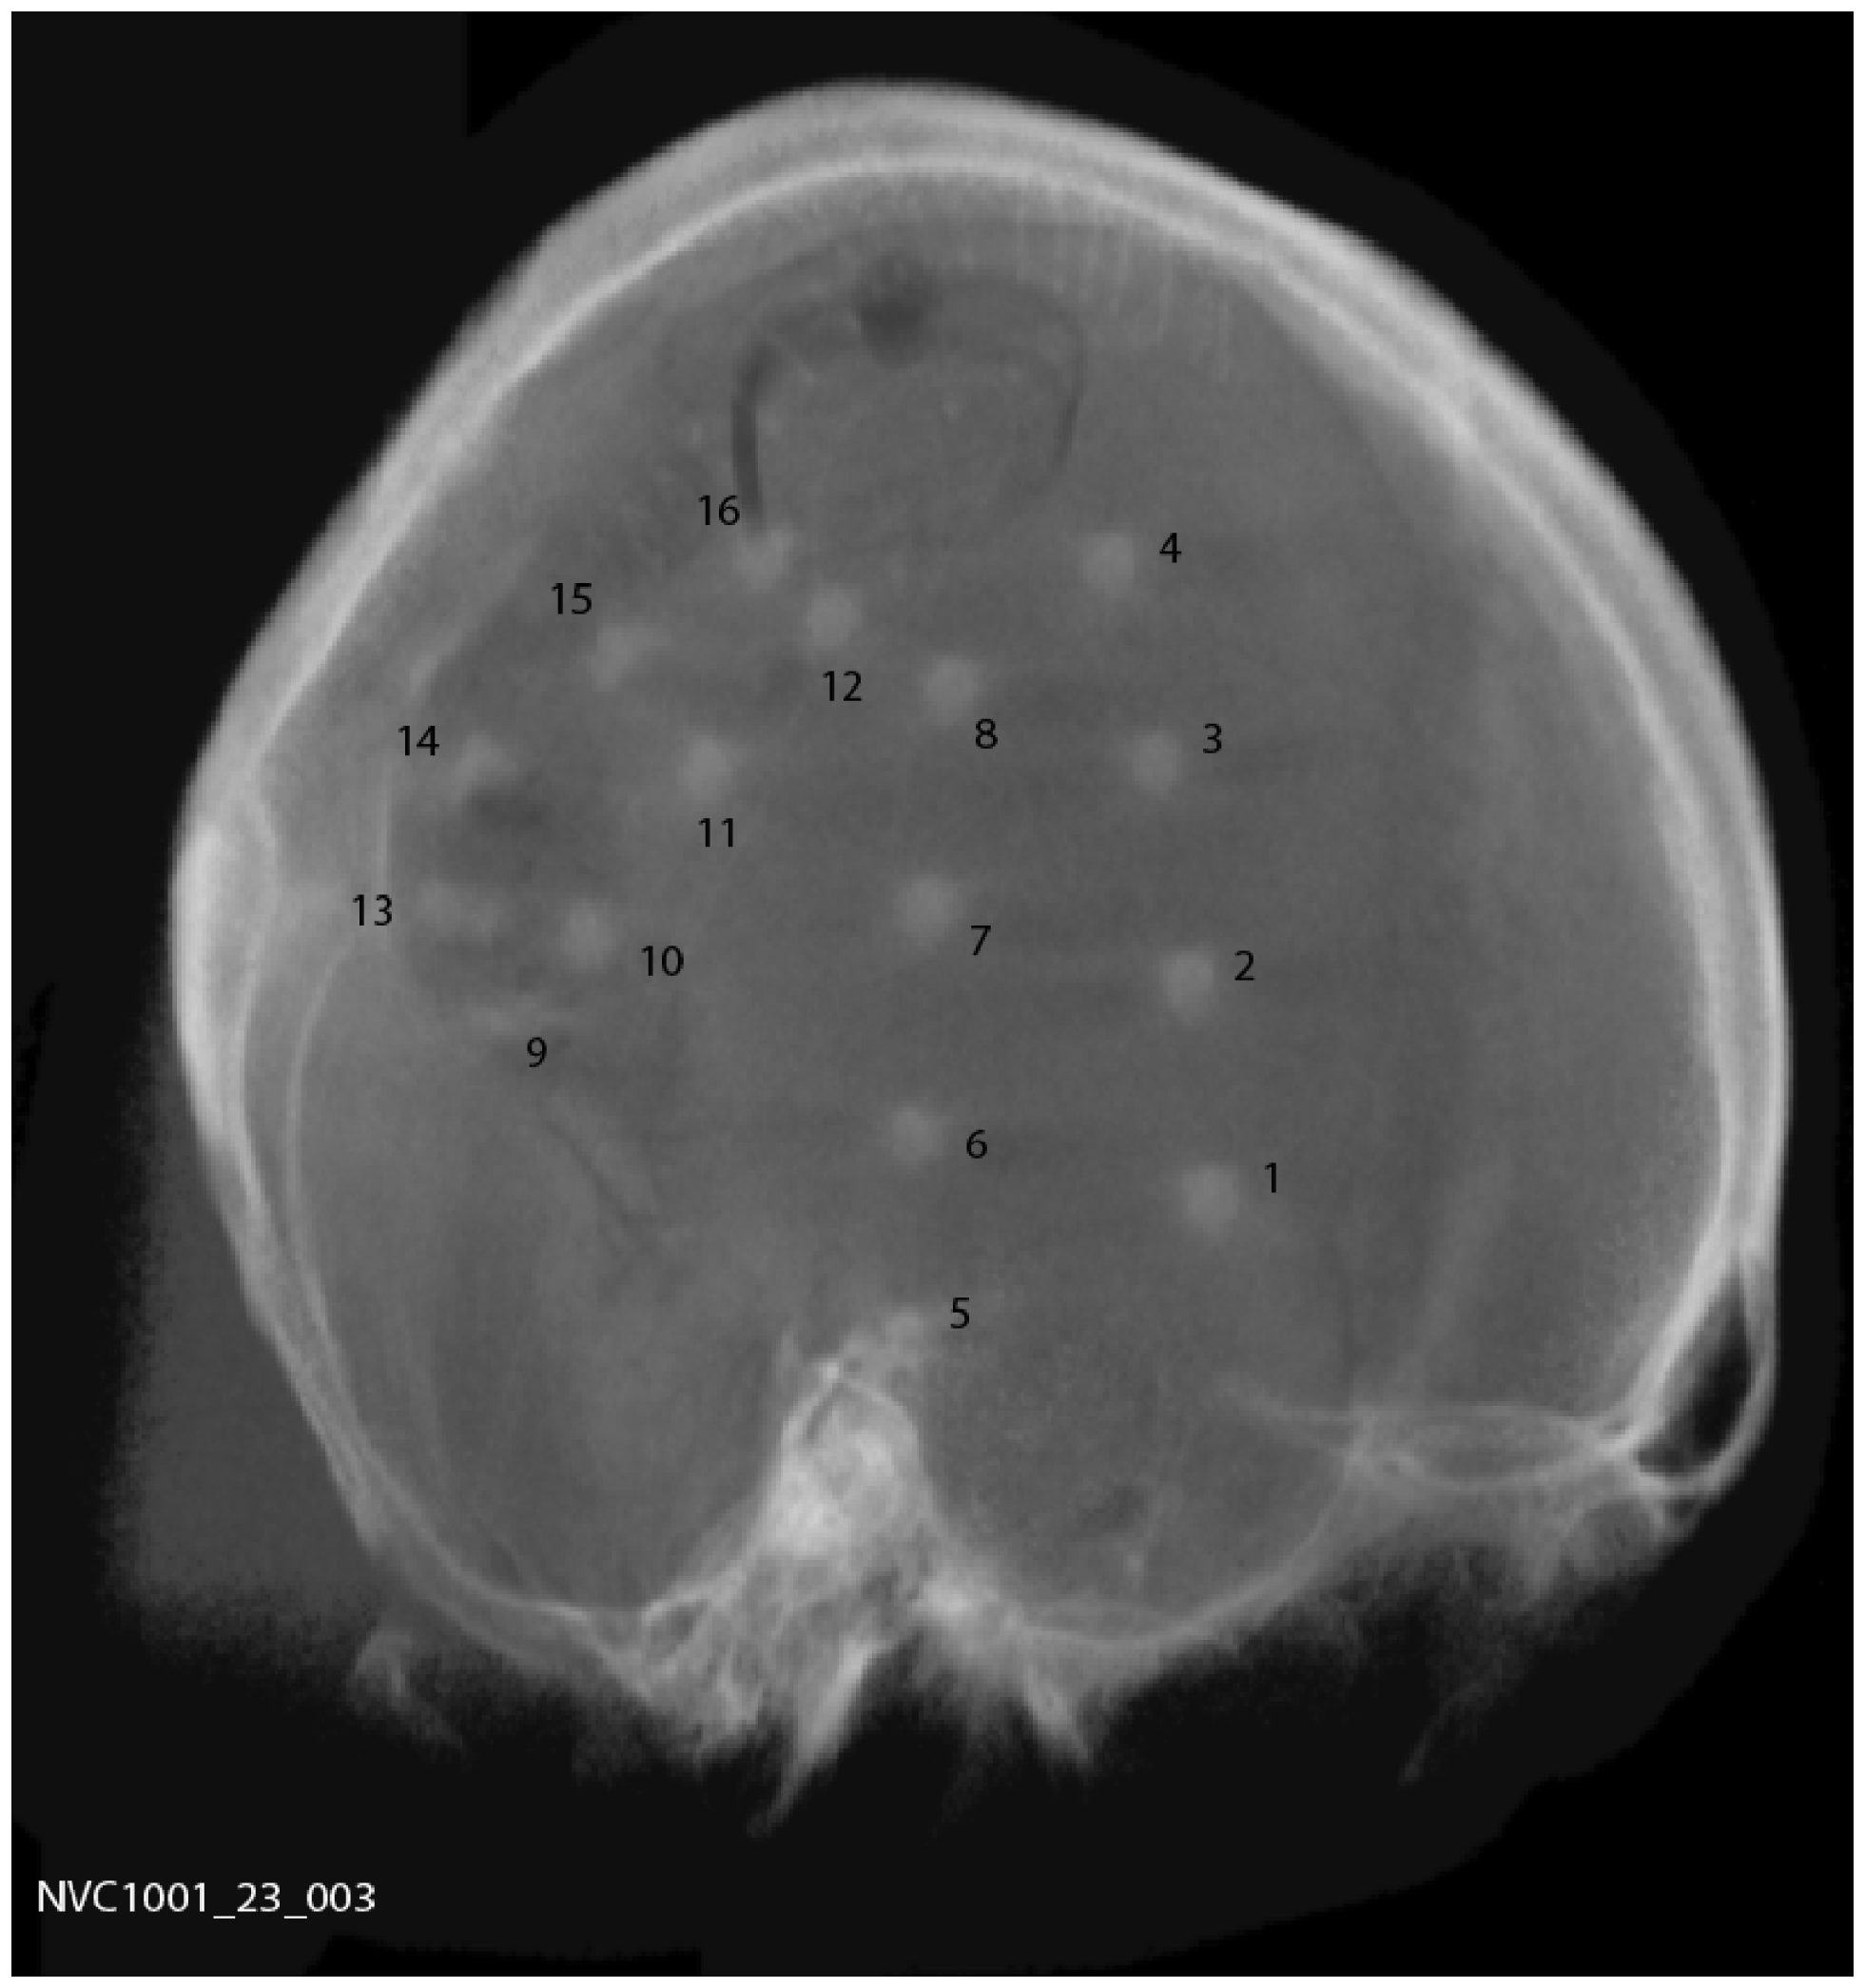

A total of 15 subjects were implanted with the device, 9 males and 6 females with a mean age of 44.5 years (range 20–62). Two silicone implantable lead assemblies, each with eight platinum iridium contacts distributed across two electrode arrays (16 electrodes in total), were used to collect iEEG on the cortical surface. Leads were placed regionally, unilaterally over the quadrant believed to contain the epileptogenic zone, as determined by prior EEG studies, imaging studies, and/or seizure etiology, via a small craniotomy or through prior craniotomy sites if surgery had been performed in the past. A typical implantation scheme is shown in Figure 1. For those subjects diagnosed with bilateral temporal lobe onset seizures, leads were placed over the hemisphere that generated the most frequent, stereotypical seizures. System operation and integrity was verified prior to wound closure. The leads were tunneled down the neck and terminated at a subclavicularly placed, titanium encased, hermetically sealed, implantable telemetry unit, which sampled 16 channels of iEEG acquired at 400 Hz and wirelessly transmitted it to an external, hand-held personal advisory device. The external, hand-held personal advisory device received the telemetered iEEG and stored iEEG on standard flash memory cards for subsequent analysis. An important component was that it also supported audio recordings, both manually triggered by the subject for diary purposes, and also automatically activated when a seizure was detected by the system to aid in establishing a clinical correlate with iEEG activity. The duration of implantation varied between ~0.5 and ~1.8 years.

Figure 1

Plain skull radiograph of subject post implantation, showing typical implantation scheme.